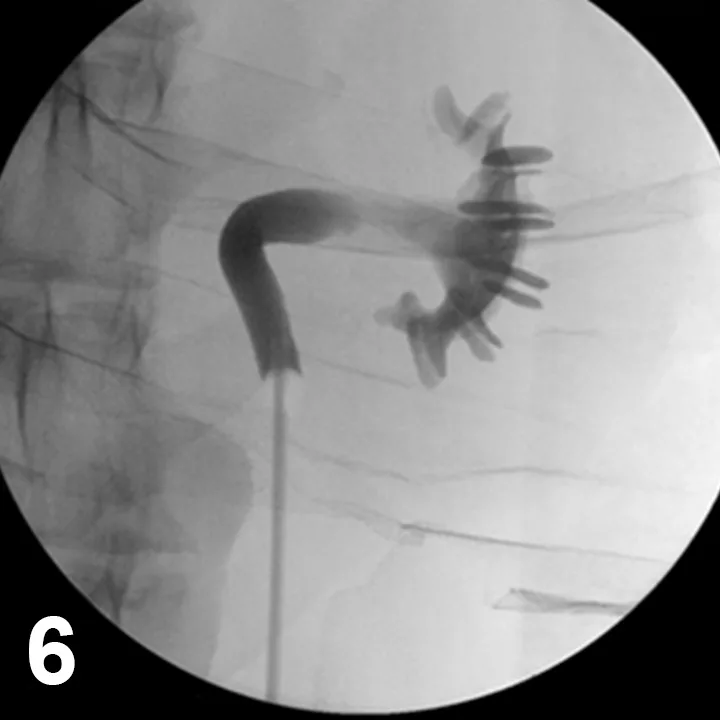

Ureteroscopy

This procedure is possible in dogs that weigh more than 15 kg. It is mainly performed for the evaluation of idiopathic renal hematuria. Ureteroscopy can be difficult to perform through a normal ureteral orifice, as the ureteral opening in a normal dog is less than 2 mm and the smallest ureteroscope is approximately 2.7 mm. Ureteral access is obtained using cystoscopic visualization with fluoroscopy (Figure 5). Preplacement of a ureteral stent may allow the ureter to dilate enough for the ureteroscope to be passed more easily.

Figure 5. Fluoroscopic images during retrograde ureteronephroscopy in a female dog. A rigid endoscope is placed in the urinary bladder (A). A catheter is advanced into the distal ureteral lumen for a retrograde ureteropyelogram. A guide wire (black arrows) is advanced through the ureter and into the renal pelvis, and an open-ended ureteral catheter (white arrowhead) is advanced over the wire (B). A ureteral dilation catheter (arrows) is advanced over the guide wire to ensure endoscopic passage (C). A flexible endoscope (arrows) is passed through the ureter and into the renal pelvis using fluoroscopic and endoscopic guidance (D).